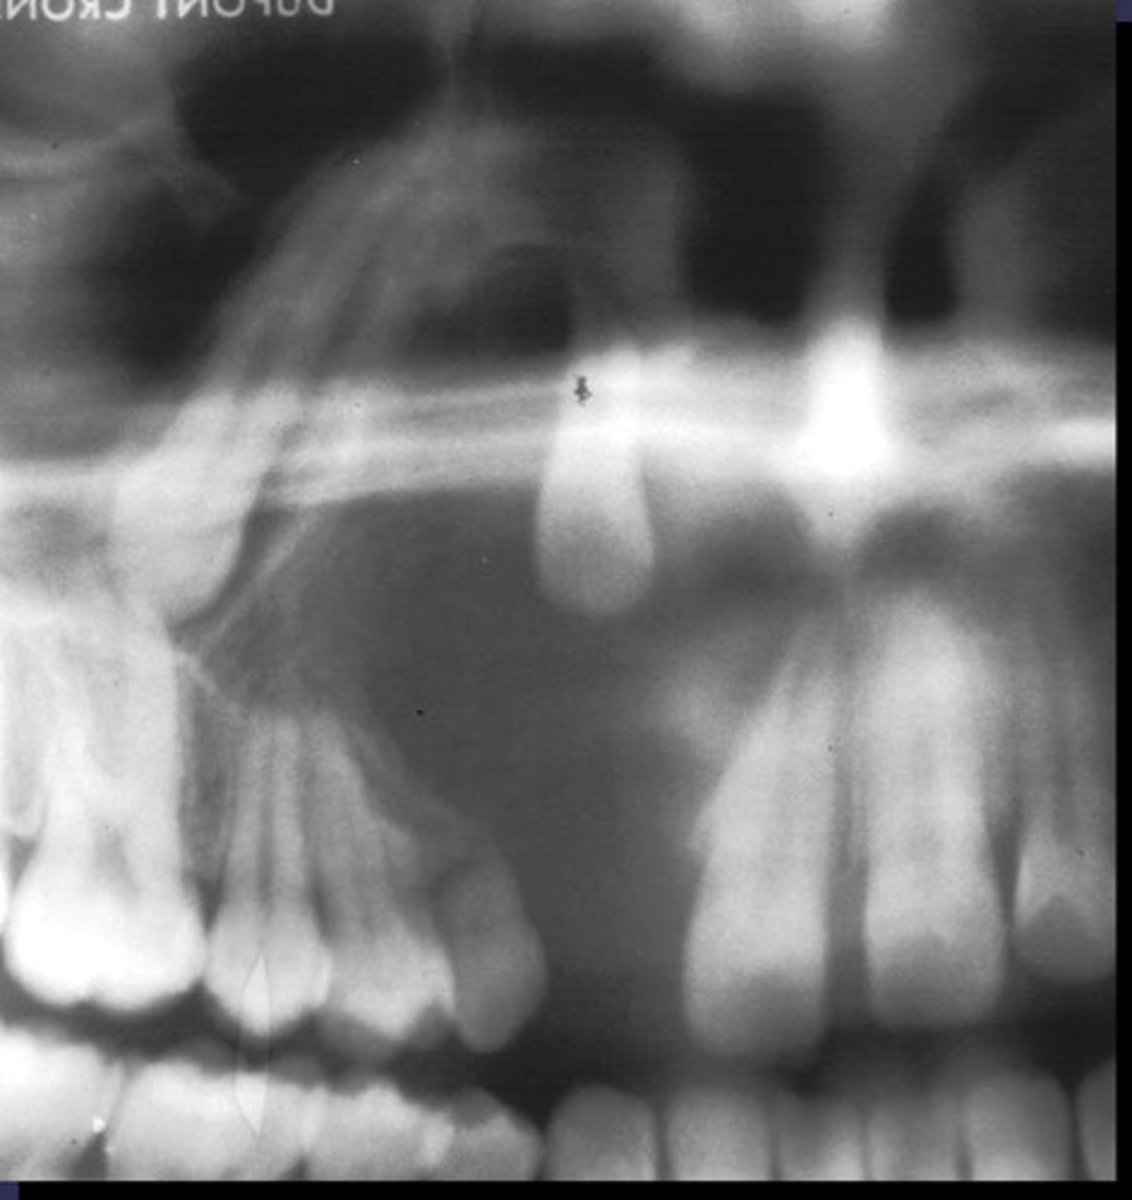

how would you describe this lesion? (not the giant cavity btw)

A. defined, corticated, periapical radiolucency causing loss of lamina dura and PDL space on #6-7

B. defined, non-corticated, periapical radiolucency causing loss of lamina dura and PDL space on #6-7

C. ill-defined, circular radiolucency located above tooth #7

D. well-defined, corticated, radiopacity

- Also note epicenter located above apex # 7 which has large dental caries.

What category would this lesion be part of?

Inflammation/benign

all of the following could be a differential diagnosis for the following lesion EXCEPT?

A. radicular cyst

B. Periapical granuloma

C. apical rarefying osteitis

D. renal osteodystrophy

what category would this lesion be classified into?

inflammatory/benign cystic